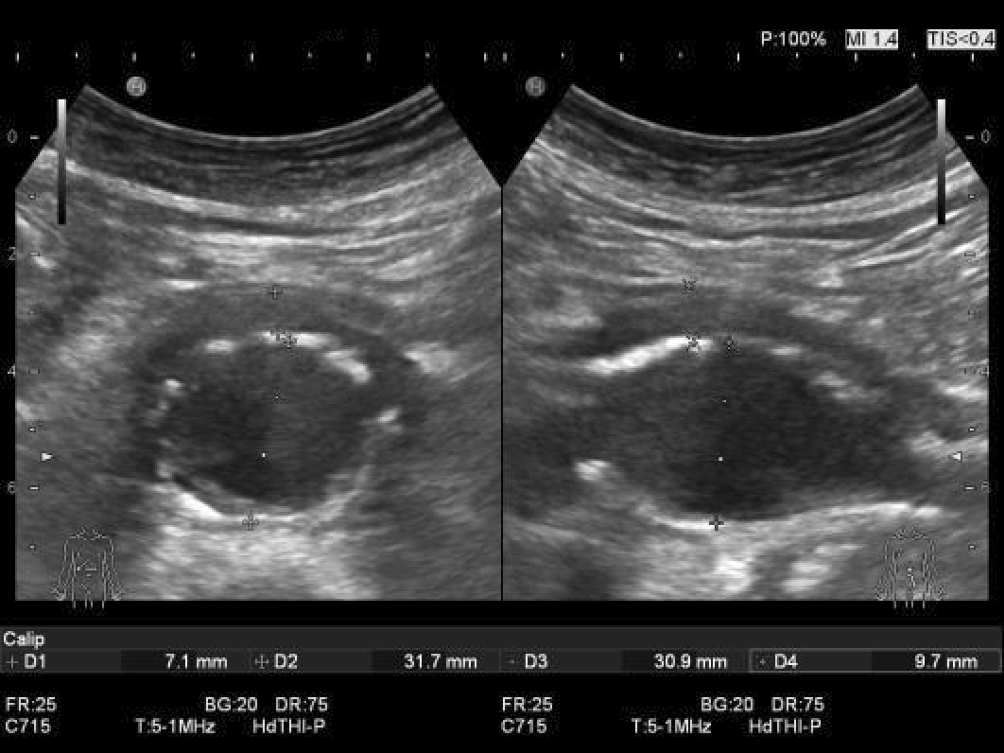

Insbesondere bei elongiertem Aortenverlauf (meist nach links-lateral) kann eine axial gemessene, ektatische Aorta fälschlicherweise als Aortenaneurysma (insbesondere bei Messung in transversaler Achse) diagnostiziert werden (Abb. 6; Videoclip 3).

Abb. 6

Ausgeprägte Aortenelongation bei einem Screeningpatienten: Der im Oberbauchquerschnitt gemessene Aortendurchmesser von 68 mm (axiale Ebene, transversale Achse gemessen) „schrumpft“ in orthogonaler Ebene (senkrecht zur Gefäßachse, transversale Achse gemessen) durch Drehen des Transducers auf den reellen Durchmesser von 28 mm (Aortenektasie; vgl. Videoclip 3)